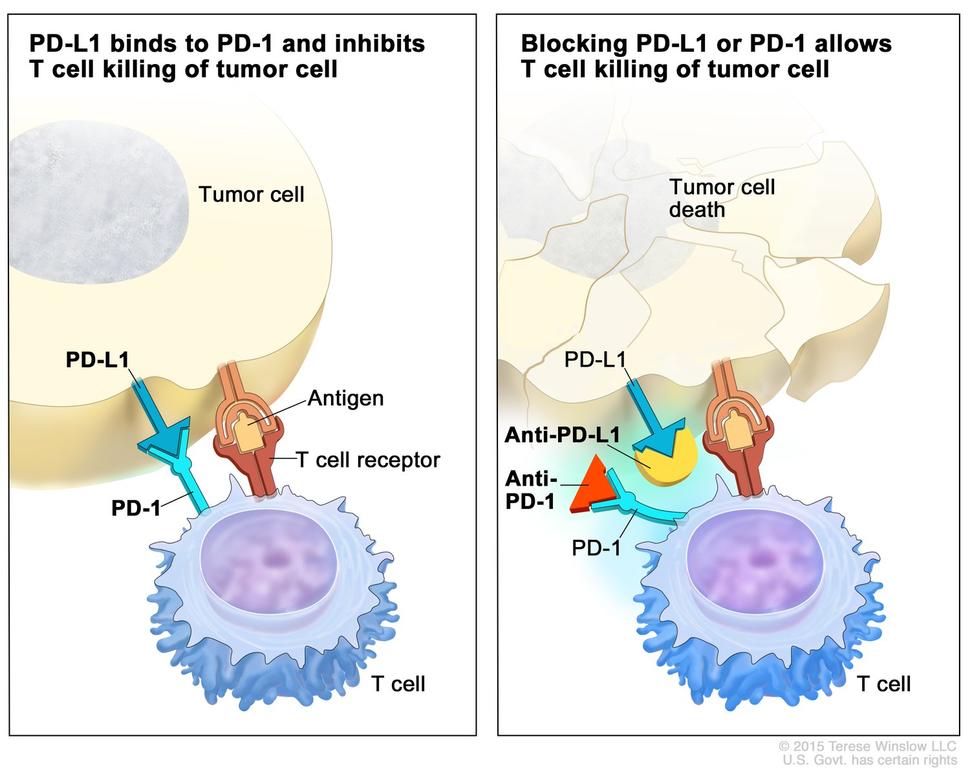

Quando o hepatocarcinoma é muito grande, são muitas lesões ou a doença do fígado ou as condições do paciente não permitem os tratamentos anteriores, ainda restam os tratamentos sistêmicos (quimioterapia). Historicamente, sabemos que o hepatocarcinoma não responde bem a quimioterápicos convencionais, o que faz um certo sentido, já que os hepatócitos em si já evoluíram para lidar com todo tipo de veneno que nós e nossos ancestrais entraram em contato. Além disso, mesmo se quisermos usar medicamentos mais tóxicos, trata-se de pessoas com fígado doente, com pouca reserva funcional e o tratamento pioraria ainda mais a situação. Assim, descobrimos que ao invés de tentar destruir diretamente o hepatócito mutante e “superpoderoso”, temos que usar de subterfúgios como retirar o suprimento de sangue e ajudar o sistema imunológico.

Hoje temos diversos tipos diferentes de quimioterápicos para o hepatocarcinoma. Os inibidores da tirosinoquinase (sorafenibe, lenvatinibe, regorafenibe e cabozantinibe) foram considerados até hoje a primeira linha de tratamento sistêmico, mas com resultados não muito animadores. Os imunobiológicos, que agem em pontos mais específicos, tendem a ser melhor tolerados e ter melhor resposta, deixando de ser usados isoladamente para agora ser indicados em duplas.

A dupla “atezo-bevo” (atezolizumabe com bevacizumabe) pode hoje ser utilizada como primeira linha no tratamento sistêmico, mas está contraindicada em pacientes com varizes esofágicas não tratadas pelo alto risco de hemorragia. Outra combinação potente que compete pelo status de primeira linha é tremelimumabe com durvalumabe.